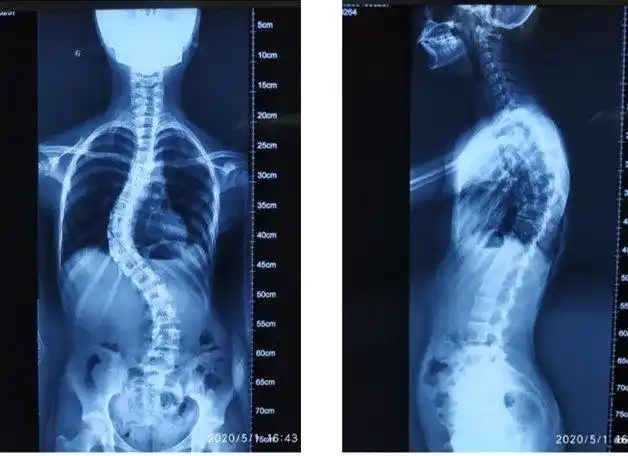

19岁女生称常年侧睡脊柱侧弯30度 成都 健康(来源:)

脊椎侧弯30度

21岁的小冀,因脊柱侧弯,脊柱成s形,身体严重歪斜

脊柱侧弯典型病例